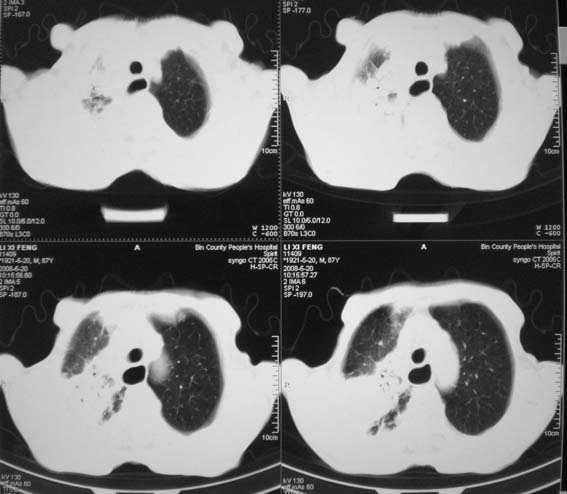

男,87岁,咳嗽、发烧、有黄痰,胸片示肺结核。

右肺上叶尖后段片状不规则致密影,密度欠均匀,相邻胸膜肥厚,纵隔内见多发肿大、钙化淋巴结,考虑为结核,部分坏死

有低密度坏死灶;结合痰检。